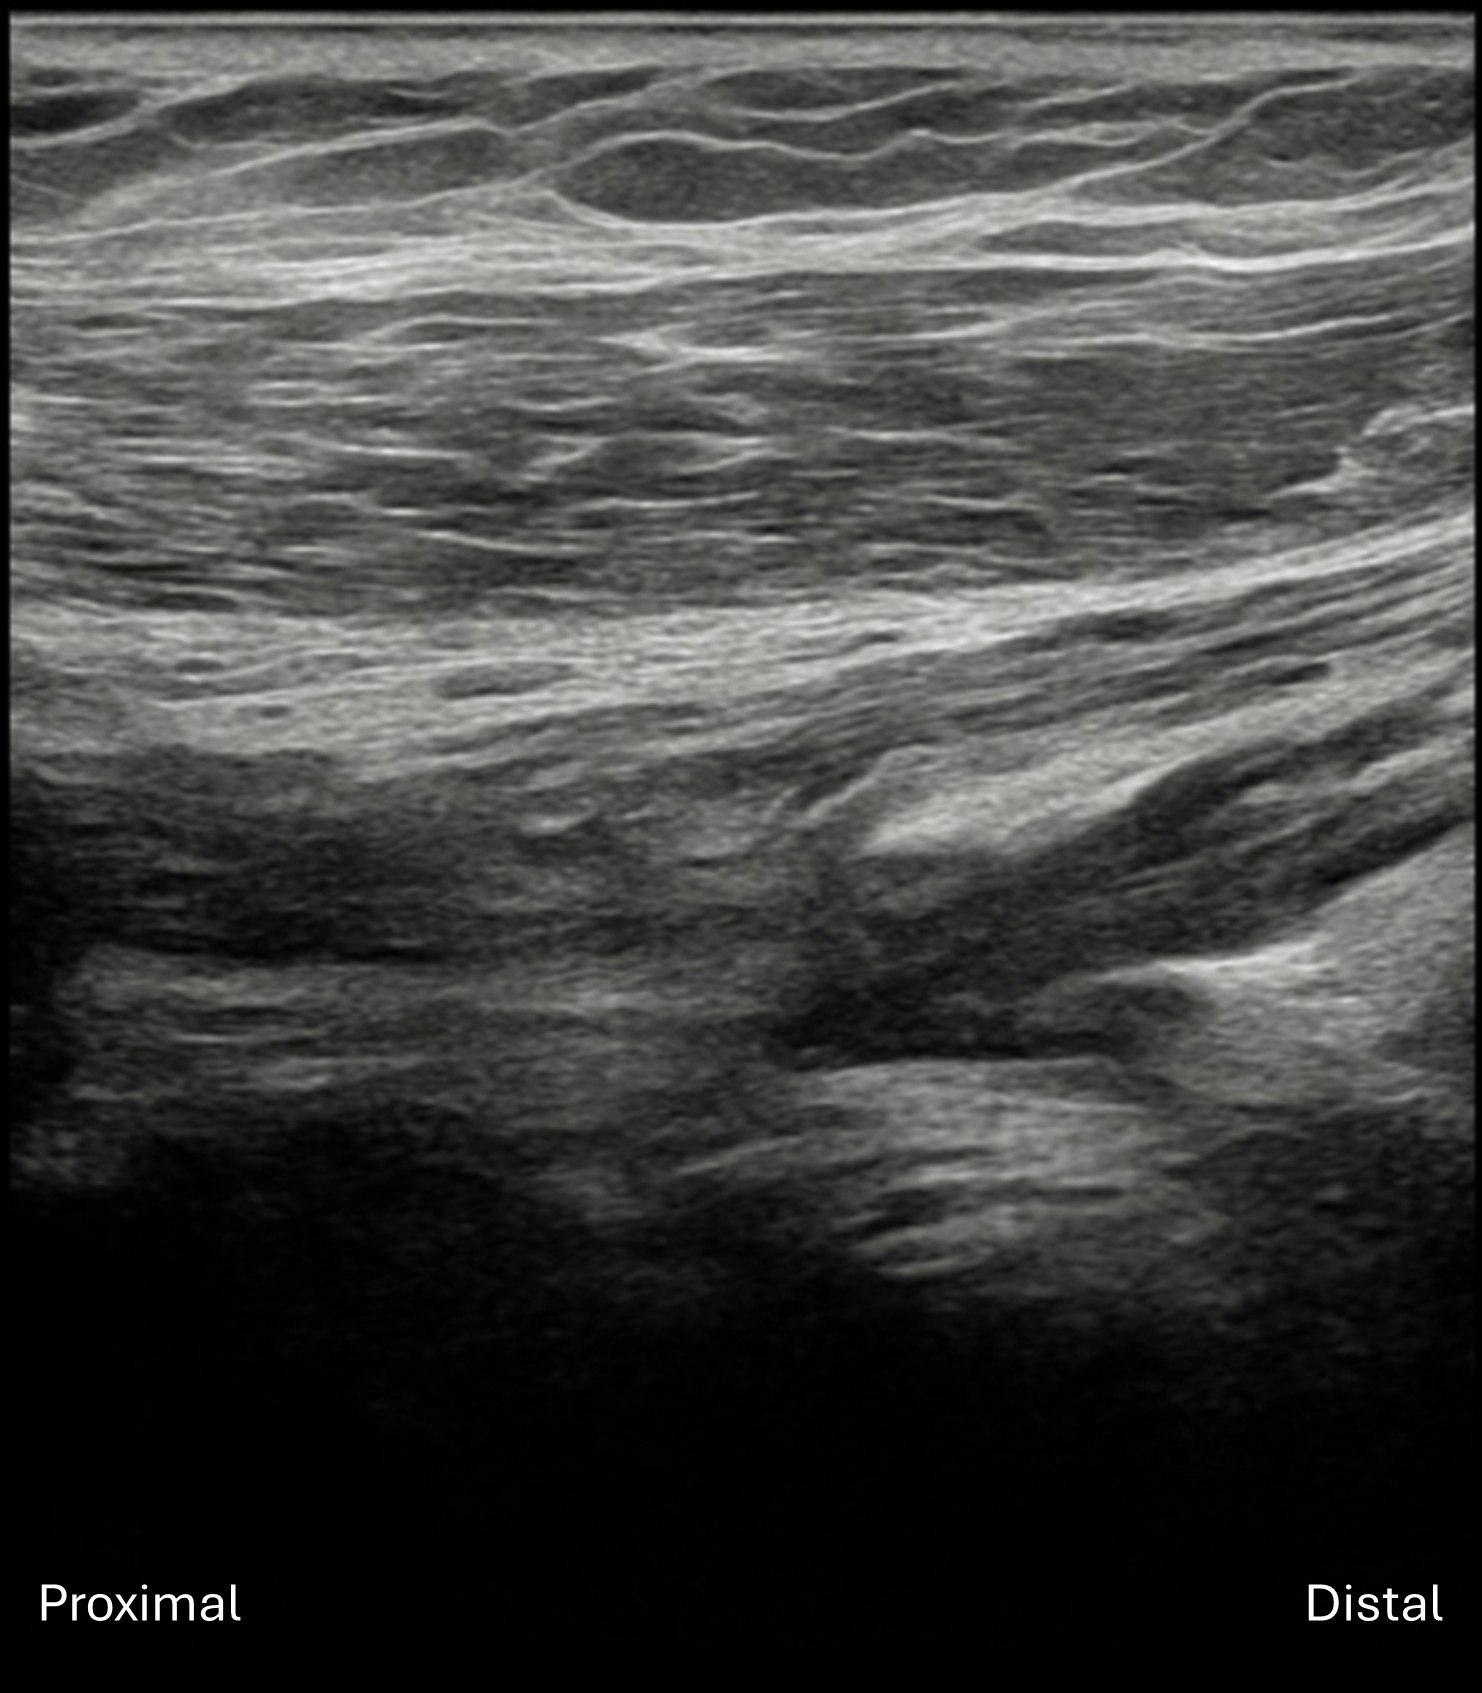

Labeled long axis view of the lateral cord of the right brachial plexus lying deep to the pectoralis major and minor muscles in the infraclavicular view. The lateral cord (dashed line) is seen to approach distal to proximal but abruptly ends (arrow) as the cord becomes focally hypoechoic and disorganized, indicating complete lateral cord transection (neural discontinuity or neurotmesis).

Unlabeled long axis view of the lateral cord of the right brachial plexus in the infraclavicular view.